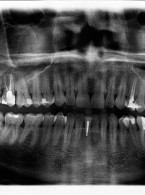

Pokrycie mnogich recesji dziąsłowych

metodą płata przesuniętego dokoronowo z wykorzystaniem przeszczepu podnabłonkowej tkanki łącznej i kolagenowego materiału ksenogennego po wcześniejszej rekonstrukcji połączenia szkliwno-cementowego - opis przypadku